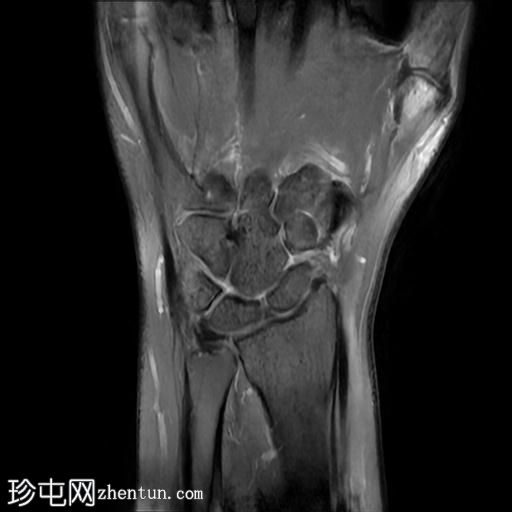

冠状位

T2加权像

桡侧腕屈肌腱鞘内可见液体信号,提示腱鞘炎

手部桡侧腕屈肌腱远端扁平,邻近的大多角骨嵴和舟骨结节可见反应性骨髓水肿

MRI结果提示存在桡侧腕屈肌腱病变,以及大多角骨和舟骨结节骨髓水肿。桡侧腕屈肌(FCR)肌腱病通常表现为腕关节掌侧(靠近桡侧)疼痛。这种情况通常是由于长期过度使用造成的,尤其是在肌腱与粗糙表面接触的部位。